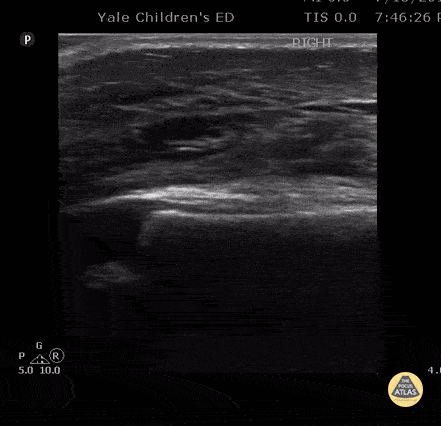

Longitudinal suprapatellar evaluation with linear probe in a 23 month old with swelling to knee / lower leg after vaccination given in thigh. Note the impressive soft tissue edema. There is no cobblestoning pattern and no fluid collection layering under the quadriceps tendon / no signs of suprapatellar effusion. The patient had a dry arthrocentesis performed under procedural sedation by a consulting service. Contributor: Antonio Riera, MD, Yale University School of Medicine